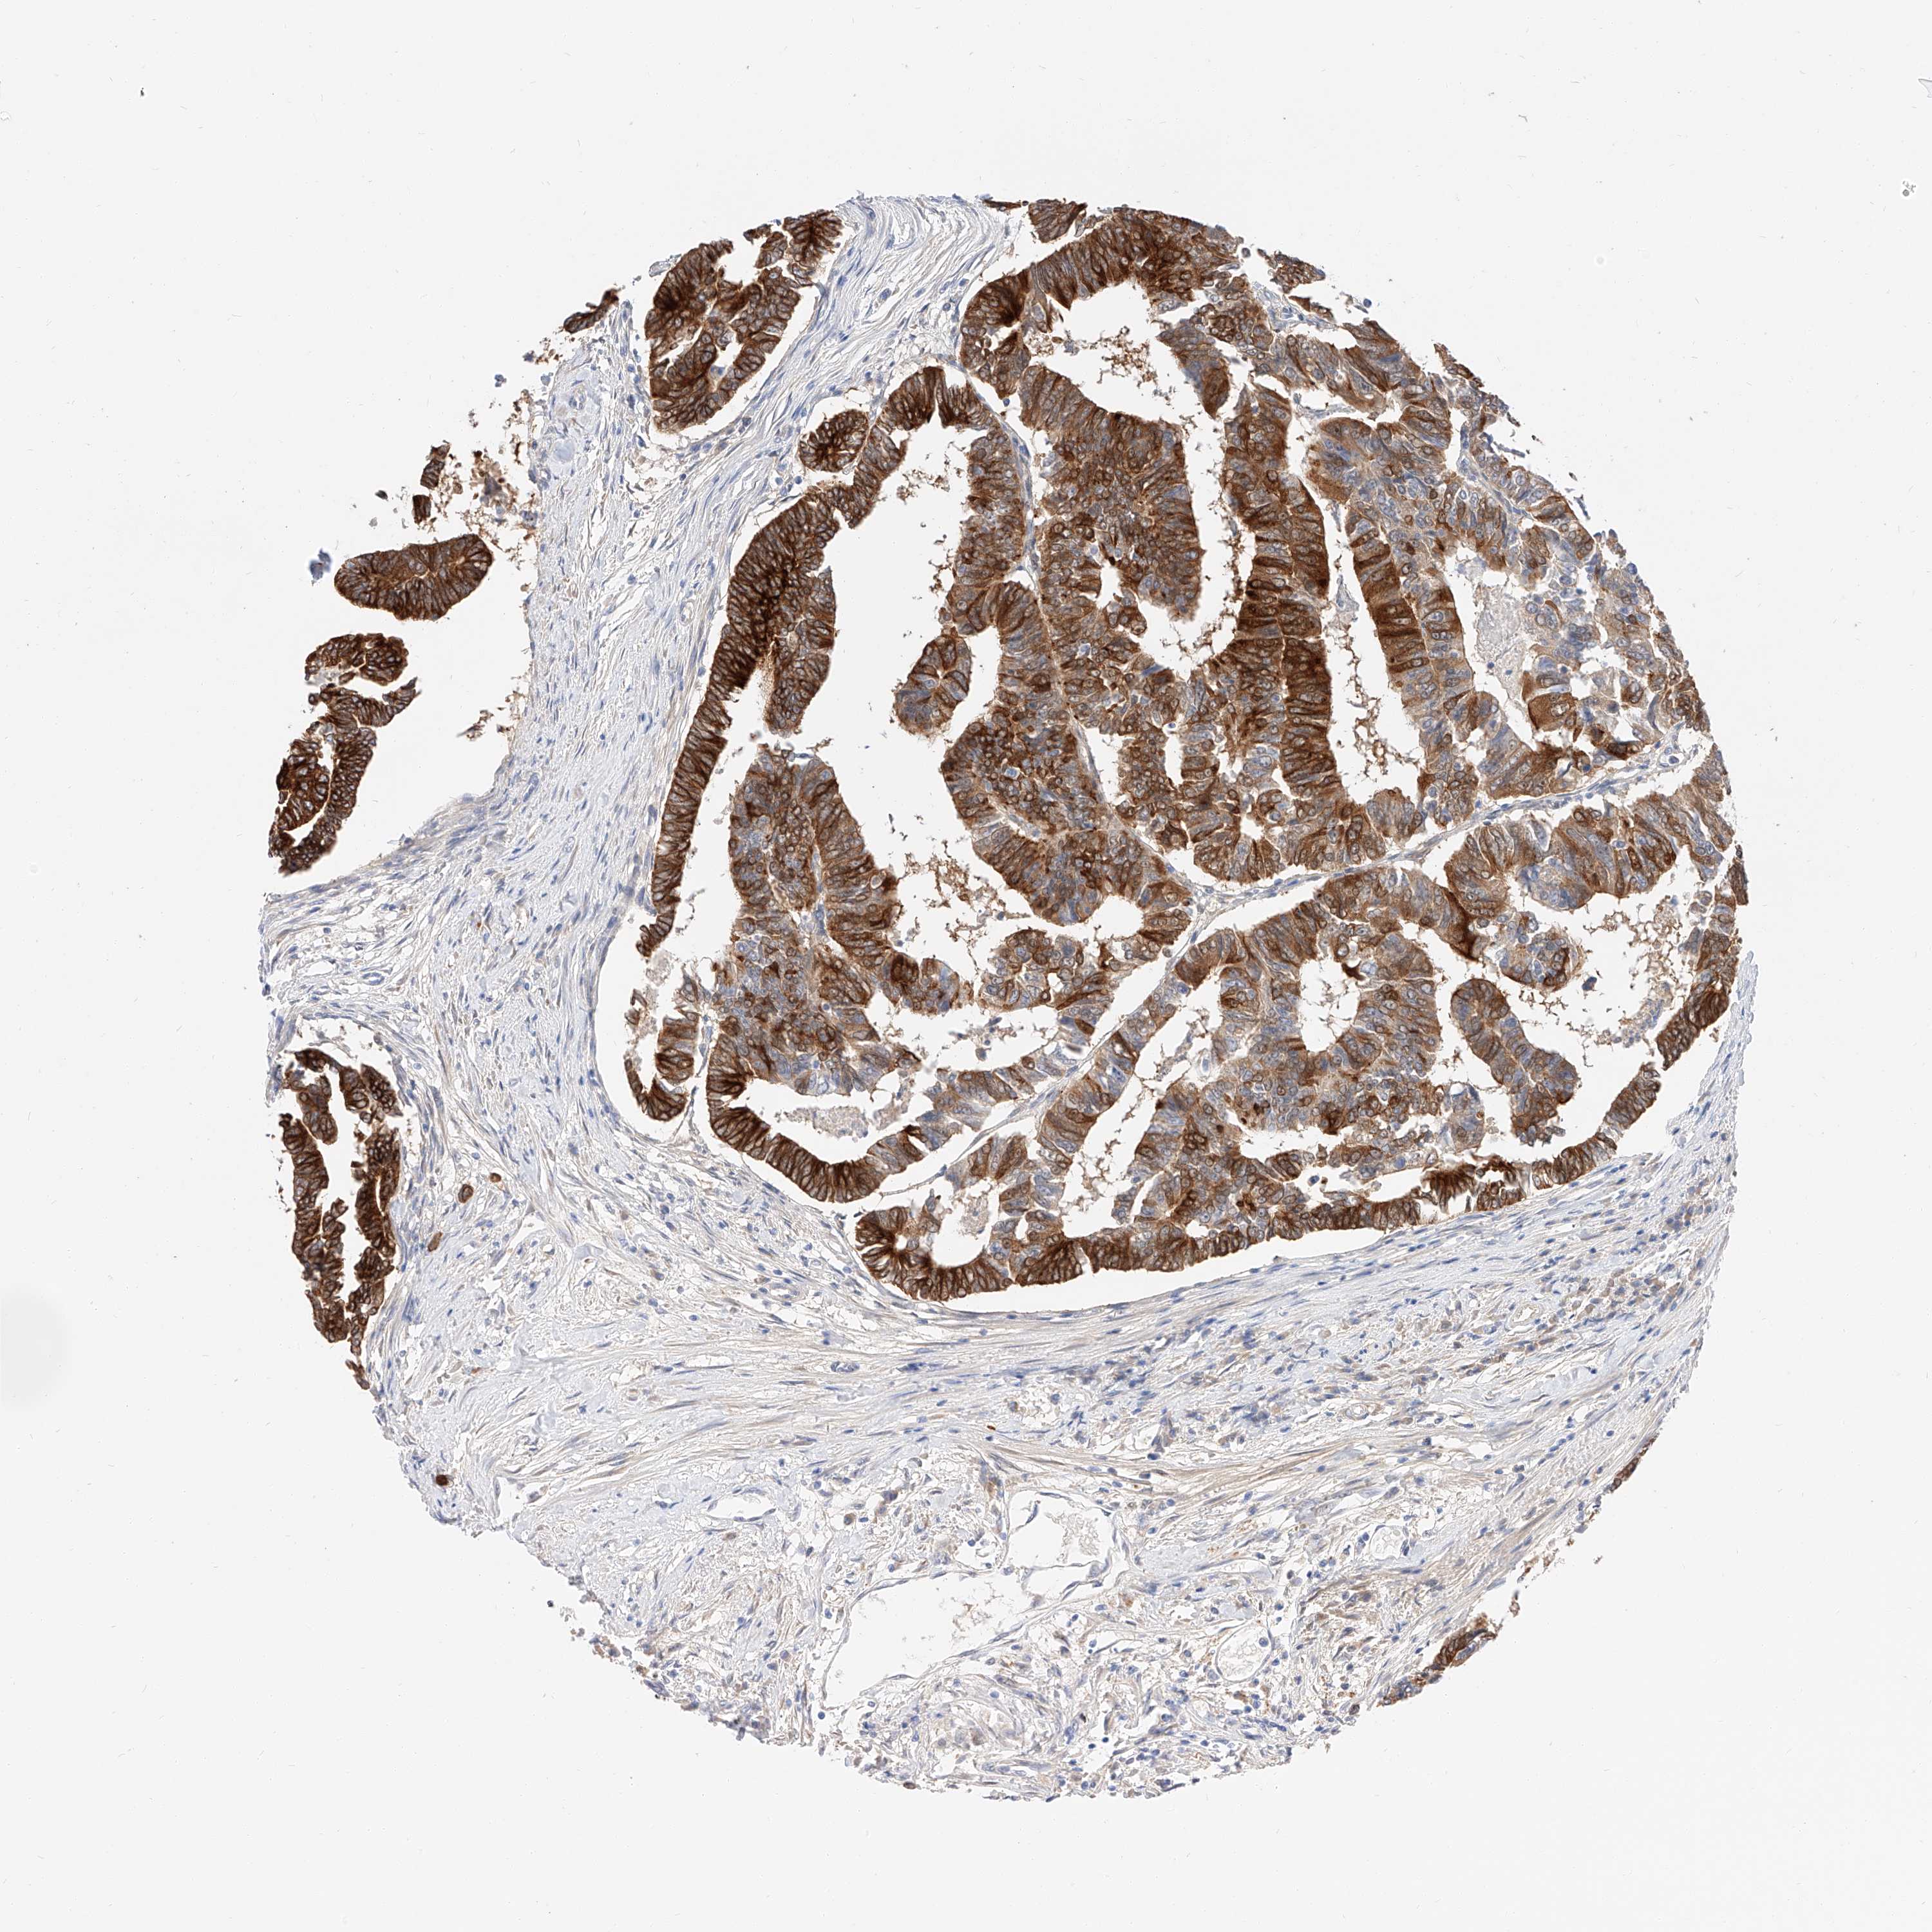

CANCER COLORECTAL CANCER Show tissue menu

COAD TCGA COAD VALIDATION READ TCGA READ VALIDATION PROTEIN COAD CPTAC PROTEIN EXPRESSION

ANTIBODIES

AND

VALIDATION